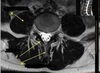

SPINAL CORD

How well did you know this?

1

Not at all

2

3

4

5

Perfectly